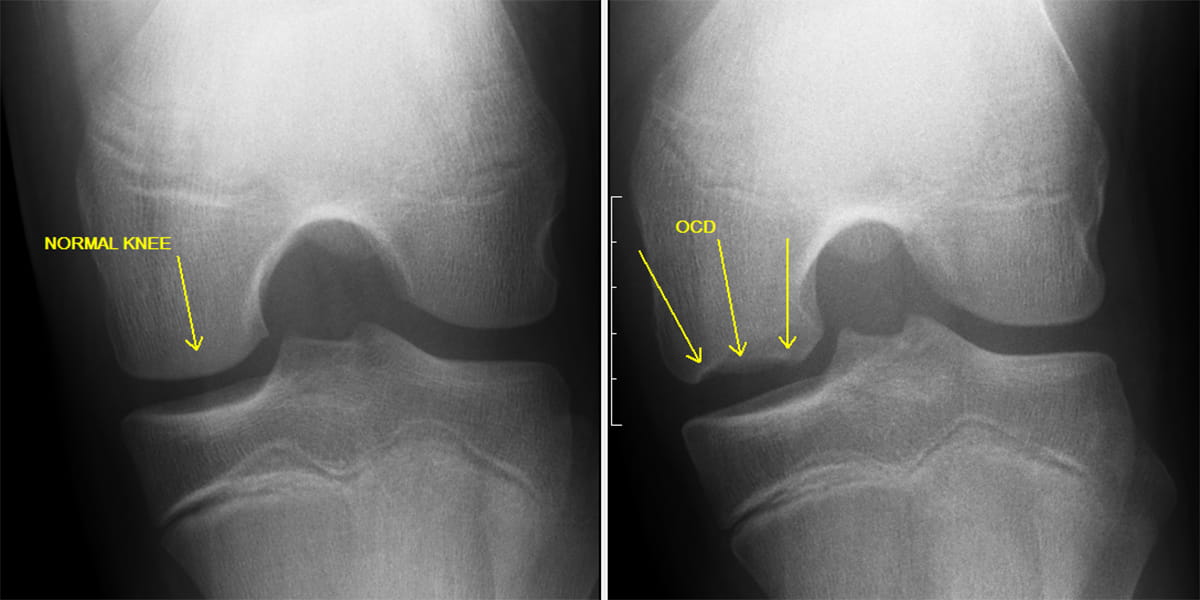

Osteochondritis Dissecans JOI Jacksonville Orthopaedic Institute Osteochondritis Dissecans — regardless of etiology, osteochondritis dissecans is an idiopathic focal joint disorder affecting the subchondral bone. — learn about osteochondritis dissecans, a pathologic lesion affecting articular cartilage and subchondral bone in the knee and other joints. learn about osteochondritis dissecans (ocd), a condition that affects joints, especially in children and adolescents. — learn about osteochondritis dissecans,. Osteochondritis Dissecans.